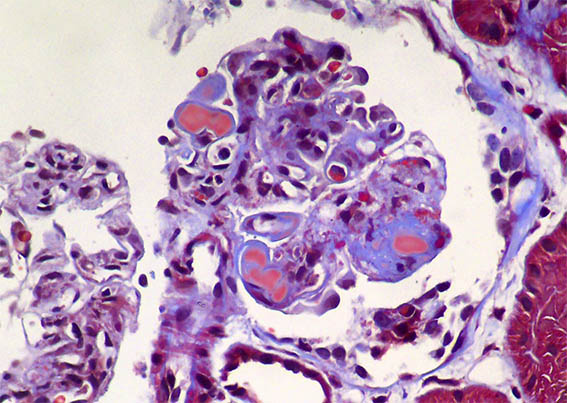

Figure 4. Masson´s trichrome stain, X400. Other capillaries with intracapillary hyaline material ("hyaline thrombi").